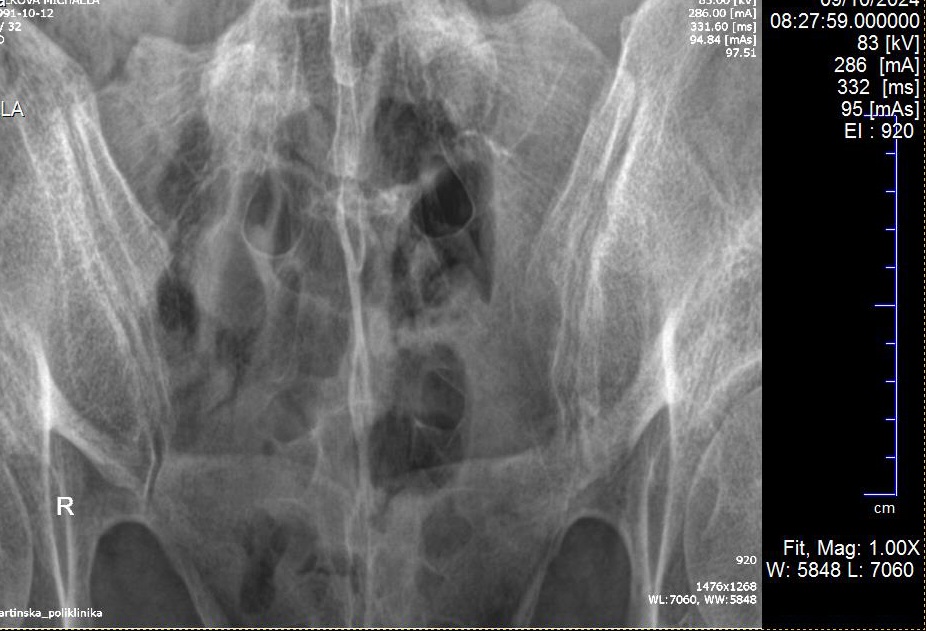

Naozaj mas pocit, ze takto jedna foto nahrana na MK kde sa nasledne o kvalite snimku neda ani hovorit bude mat vypovednu hodnotu?

neexistuje aby ti to niekto popisal. Medicinske obrazky sa prehliadaju v specialnom prehliadaci na kompoch kde si mozes dynamicky menit hodnoty sedej hore a dolu a iba tak vidis co vidiet mas. Dokonca mas popri tom presne definovane svetelne podmienky v miestnosti ked to kukas. Vsetko ostatne je zivotu nebezpecne